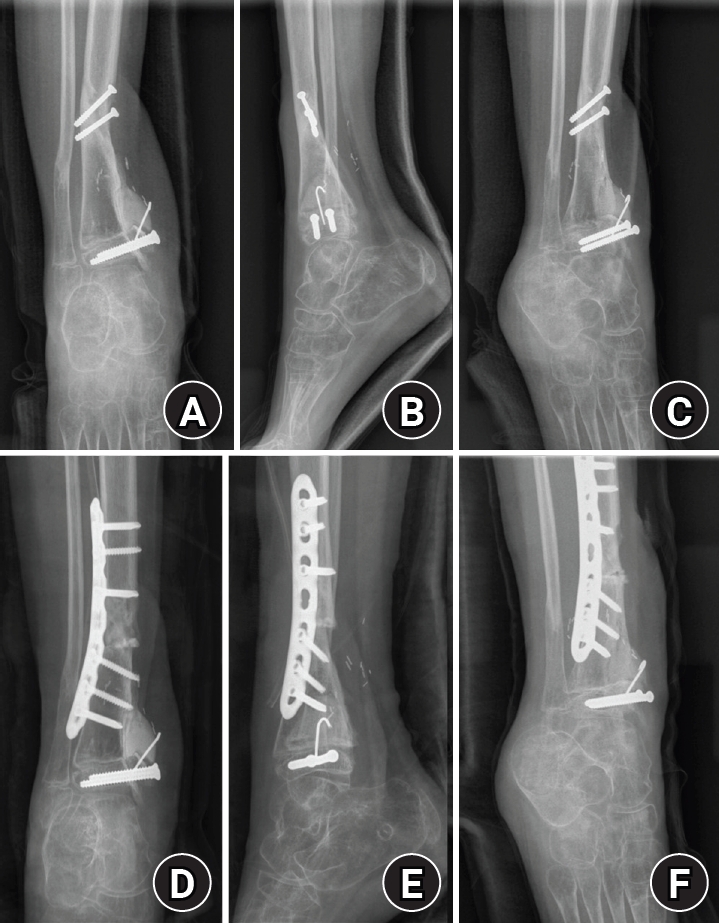

An 8-year-old girl presented after a traffic accident with a severe crush and degloving injury of the medial right ankle and foot, a distal tibiofibular fracture, and medial midfoot bone defects. After staged irrigation and debridement with temporary external fixation, definitive reconstruction was performed on August 6, 2016. The medial malleolar defect (2.5×2.0 cm) was reconstructed using a contoured autologous iliac crest bone graft secured with internal fixation, and medial stability was augmented using harvested gluteal fascia as a deltoid ligament substitute fixed with suture anchors. A bone-cement spacer was placed adjacent to the injured physis to mitigate physeal bridging, and the extensive soft-tissue defect was covered with a free anterolateral thigh flap and skin graft. During follow-up, progressive varus deformity and contracture were managed with corrective osteotomy and plating, Achilles tendon lengthening, Z-plasty, and Ilizarov fixation. At the final follow-up (March 6, 2025), the limb-length discrepancy was 5 mm, active ankle dorsiflexion was 0° (passive dorsiflexion 5°), and the patient was pain-free with full participation in daily activities, including hiking and dancing. This case emphasizes the value of an integrated staged strategy that combines bony reconstruction, medial stabilization, physeal management, and durable soft-tissue coverage during skeletal growth.